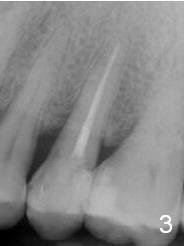

A 48-year-old man (CM) finished root canal therapy for the tooth #13 2.5 years ago (Fig.1). The tooth fractured lately (Fig.2). In spite of the fact that there is no periapical radiolucency in the most recent PA (Fig.3), the socket will be treated with No Antibiotic. Osteotomy is initiated at the junction of the lower and middle thirds of the palatal wall. The palatal cusp subgingival fracture may cause bone resorption in the palatal wall (at the crest). A 14 (Fig.4) or 13.5 (Fig.5) mm bone-level implant is probably going to have 8 mm contact with new bone.